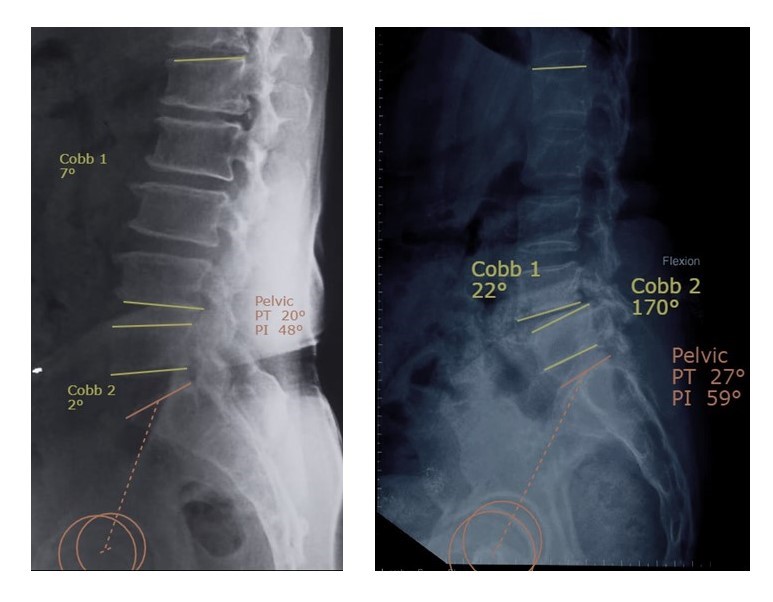

After scanning the lateral radiographs, Surgimap spine software was used to draw all the above-mentioned independent variables. The Surgimap Spine is a free computer program (http://www.surgimap.com; Nemaris Inc., New York, NY, USA) that integrates the spine‑related measurements and tools for surgical planning in combination with knowledge gained from the published literature. After importing preoperative digital radiographs into a Surgimap Spine customizable database, measurements and alignment planning were executed. The software program calculates angles in degrees. Fig. 1 is an illustration of various angles measured by the surgical software.

This table of multivariate logistic regression shows that the PI and disc angle have a significant impact on the outcome with adjusted odds ratio of 1.127 and 1.299, respectively. This means that the DSL group has a significantly higher value of PI and disc angle than DDD Group. A representative case and its graphical representation are given in Fig. 2 and 3.

Figure 2: Case illustration of non-listhesis patient and listhetic group patient.

This study compares 2 groups of patients who underwent surgery for single-level DDD of the lumbar spine at L4-5 level – a group without and with DSL of the affected segment. There were 3 salient observations in the study population – the PI in the DSL group is significantly higher than the control group. Similarly, the PT is also higher in the DSL patients. Segmental disc angle measured at the L4-5 (slip level) is almost always less lordotic in the DSL group compared to the non-listhetic group (Fig. 4). ROC curves were used to study the cut-off values of each of the 3 statistically significant parameters. A PI of >48.8° was found to be predictive of DSL, while a PT of >16.75° and a disc angle of >−8.05° (implying more segmental kyphosis) were deemed threshold values for predicting DSL. The study also observed that total LL does not vary significantly between the groups and therefore cannot be used as a predictor of DSL. Since the total LL is similar in both cohorts and the segmental lordosis significantly different, there must be a compensatory change above or below the L4-5 level; L5-S1 being relatively fixed, one might assume that maximum difference in the sagittal plane is between L1 and L4 end plates. Another interesting observation is related to the station (position) of the L5 in relation to the pelvis. Patgaonkar et al. classified the L5 position into 3 locations depending on the relationship of the inferior border of L5 vertebra to the intercristal line [15]. These authors use the terms fully incarcerated, partially incarcerated, and standing proud for the 3 levels described. It was assumed that the location of L5 might influence the mobility of the L4-5 motion segment and therefore in some manner predispose to DSL. Such was not the case based on this study, i.e., all 3 variations in L5 station seemed to have equal predilection to develop DSL. DSL primarily occurs at the L4-L5 level. In their landmark study, Gille et al., found that the slippage was located at L5-S1 in 6% of cases, L4-L5 in 73%, L3-L4 in 18%, and L2-L3 in 3%; 12% of patients had slippage at two or more levels [16]. Researchers have attributed the etiology of DSL to several factors such as pregnancy, generalized joint laxity, and oophorectomy, mainly due to its preponderance in women [17,18,19]. Sengupta and Herkowitz observed that sagittal orientation of the facet joints and increased pedicle-facet angle as predisposing factors [3]. In yet another study, Rothman et al., reported that forward subluxation is primarily a disease of the posterior joints and is found most commonly at L4–L5, whereas retrolisthesis is a primary disorder of the disc space and is noted more commonly at L3–L4. However, the exact etiology of DSL still remains elusive [20]. A number of papers have also appeared studying the influence of SPPs on DSL. The French Spine Society published their study of DSL in 2014 and 2017, describing 3 categories of degenerative slips based on the spino-pelvic alignment [16,17,18,19,20,21]. These authors described a small number of patients with <25° of PT while a much larger number had >25° of PT. Both groups had large PIs (and PI-LL >10°). In their study, a significant number of patients had sagittal vertical axis (SVA) >40 mm, suggesting gross sagittal malalignment. This was not measured in any of the patients in our cohort but it is assumed that the difference in ages of the samples was the cause of the difference; our patients were much younger than the French study. It appears that nearly all our cases fit into the Type 1B described by these authors (segmental lordosis altered but LL preserved). The authors of the French study had only 3/166 patients in this subgroup while all our patients seemed to fit in this category. However, our patients were not analyzed for global sagittal parameters and these observations are only based on regional parameters. The threshold value for PT has been 25° in the French study (above which the authors call the slip a type 2B). Barrey et al., demonstrated a significant greater PI in patients with DSL than the normal population, suggesting that the shape of the pelvis is a main predisposing factor for DSL [11]. They reported 60° of PI in their study with DSL while our threshold was 49°. Interestingly, these authors propose that the higher PI is associated with higher LL and SS which in turn predisposes to the slip due to gravity. Other studies, including our own, have not been able to show that DSL cases are associated with higher LL and SS. In our study, the DSL cohort had loss of lordosis, tendency to anterior sagittal unbalance, and less SS, reflecting the pelvis back tilt of these patients. Similarly, Morel et al., also established that DSL patients demonstrated a significantly higher PI (62.6°), a loss of LL, and a decrease in SS [22]. Recently, Fei Han et al., conducted a study of the SSPs in patients with lumbar DS [23]. Interestingly, these authors also found a high PI in patients with DS but the PI was even higher in patients with associated DLS than those without. They attributed this high PI to the high prevalence of DLS among DS patients. Kobayashi et al., study also identified large PI as one of the risk factors for the SVA deterioration of DSL. Clearly, the evidence thus far suggests that PI may be involved in the onset and progression of DSL [10]. The present authors found that PI and PT were significantly larger and LL and SS were significantly smaller in the DSL group than in the Control group. Borkar et al., published the SPPs in the normal and pathological states in Indian population [13]. These authors found PI in the asymptomatic individuals was 49.29° ± 5.95°, which was significantly lower when compared P < 0.001) to DSL patients (59.4° ± 21.33°, P < 0.001), and failed back surgery syndrome (56.7° ± 8.21°, P < 0.001). The mean PT in healthy controls was 14.3° ± 4.08° which was significantly lower when compared with patients of lumbar listhesis (23.35° ± 14.03°, P < 0.001) and failed back surgery syndrome (22.8° ± 8.09°, P < 0.001), whereas SS and SVA offset did not show any statistically significant difference. Our data also substantiates these results. In the Borkar et al., study, the mean LL measured in healthy individuals was 42.5° ± 7.89°, which was significantly lower than patients with lumbar listhesis (46.24° ± 19.24°, P = 0.04) [13]. Barrey et al., also observed that >85% of DSL cases belonged to Roussouly and Pinheiro-Franco spino-pelvic morphotypes 3 and 4, which is perhaps self-evident because the latter types are associated with high PI values [11,24]. However, Roussouly 4 is typically associated with high SS and LL and low PT which has been contrary to our study findings where the mean SS was 33.65° and the mean LL was 45.01° in the DSL group. Although our study did not explicitly look at the Roussouly types, it is evident that most of our cases would belong to the Type 3 variant (rather than type 4). What then is the value of analyzing these sagittal pelvic parameters in DSL? One is of-course to determine the etiological association of spino-pelvic measures and DSL. In addition, many authors have also shown that restoring the sagittal alignment (particularly PT) can result in better clinical outcomes in DSL [25,26,27,28]. Evidently, individuals with higher PI seem to have a greater propensity to develop listhesis compared to their lower PI counterparts in the event of L4-5-disc degeneration. This seems to match the observations of several authors like Barrey et al., Morel et al., Sun et al., Gille et al., Kobayashi et al., etc., [10,11,21,22,28]. The current study also demonstrates increased PT (and lesser SS), implying a pelvic retroflexion in most cases of DSL. Barrey et al., also describe this loss of LL and the anterior shift of the C7 plumb line. Indeed, Gille’s study does describe a subgroup of patients with normal PT (Type 2A – PT <25), though the numbers of this subtype in their series were small. Moreover, their study describes a fairly large number of patients with preserved segmental lordosis (the authors do not describe how this parameter was measured). The major observation in the current study is the occurrence of reduced disc space lordosis at the L4-5 level while the total LL measured between L1 and S1 remains unaltered compared to controls. The threshold value has been determined to be −4.3° meaning that if the segmental lordosis at L4-5 in a degenerate disc is below this value, it acts as a protection against listhesis at that segment. The authors do agree that it is possible that this segmental disc angle at the L4-5 is likely an effect rather than the cause of the listhesis. This study has certain unique features – firstly, all the patients were operated cases in whom adequate non-operative treatment was tried and they remained sufficiently symptomatic to warrant surgery. Although this study did not have asymptomatic controls, the data suggest that SPPs could have a bearing on symptomatic DDD and symptomatic DSL. The other major advantages of this study are that it is the only study thus far that compares DSL patients with L4-5 degenerative patients without listhesis. Most available literature compares them with normal volunteers. This renders the study the ability to differentiate the precipitating cause of listhesis in a L4-5 degenerated individual and to determine whether it is indeed related to the sagittal pelvic parameters as postulated. This study also has certain limitations. First, it is a retrospective study and the numbers are rather small. The study does not look at outcomes in relation to the variables observed. The X-rays used were standing lateral views of the lumbar spine and the pelvis. Whole spine lateral images and EOS were not available to the authors for the study. Other SPPs notably SVA and coronal spine parameters were not measured in our study. Similarly, facet orientation and degeneration which also might play an important role in DSL were not taken into consideration in our study. While this may have a confounding impact on the study results it is not something that can be addressed in a retrospective study of this nature since CT scans are not routinely performed at our center in DSL cases. Global sagittal plane measurements like SVA and T1-Pelvic angle were not studied in this submission.